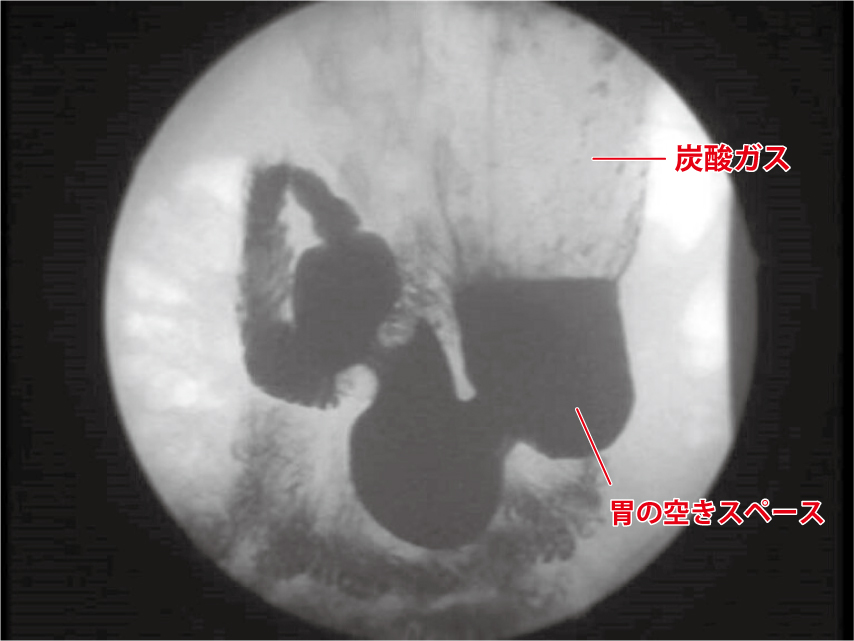

500ml飲んだとき

▲胃が炭酸水の液体の部分と気体の二酸化炭素で満たされて、胃のスペースが少なくなっています。脳の満腹中枢が刺激されるため、食欲が減退します。